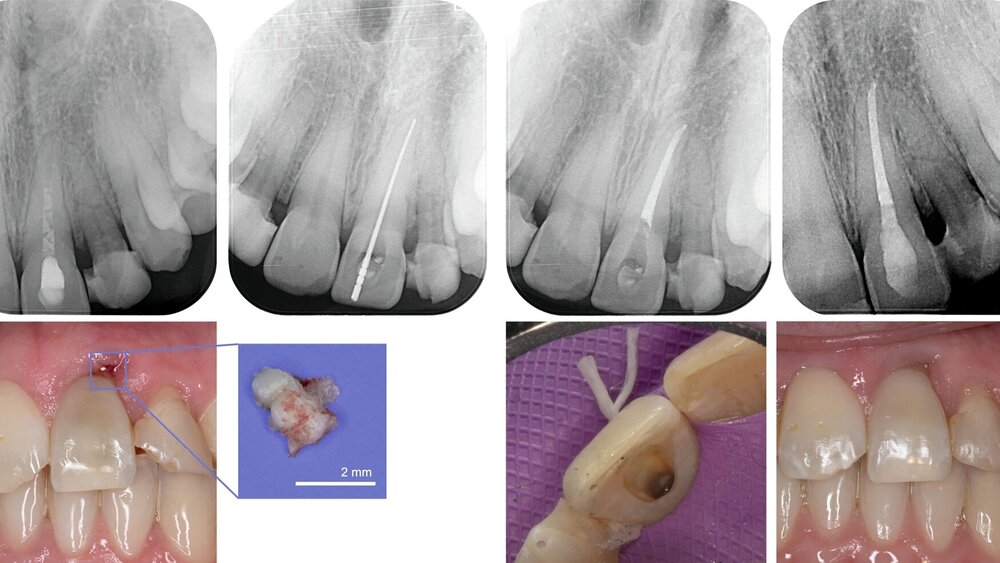

Zunächst wurden die Fremdkörper aus der Oberlippe entfernt und die Riss-Quetsch-Wunden chirurgisch versorgt. Unmittelbar im Anschluss wurde die Alveolarfortsatzfraktur in Regio 21/22 operativ repositioniert. Zur Stabilisierung der dislozierten Zähne 21 und 22 erfolgte eine flexible Schienung mittels Titan-Trauma-Splint (TTS) unter Anwendung der Säureätztechnik, wie sie bei traumatisch gelockerten beziehungsweise dislozierten Zähnen indiziert ist [Von Arx et al., 2001]. Auch die Entscheidung für eine rigide Schienung wäre im Hinblick auf die Alveolarfortsatzfraktur möglich gewesen [DGMKG und DGZMK, 2022]. Nach Reposition und Schienung wurde zur Lagekontrolle eine Röntgenaufnahme angefertigt (Abbildung 2A).

Zahn 21 war klinisch bereits repositioniert, im zuvor erstellten CT ließ sich jedoch das Ausmaß der Dislokation ablesen. Es lag eine Verlagerung der Inzisalkante nach palatinal von etwa 4 mm vor. Die Befundlage, bestätigt durch die ausbleibende Reaktion bei Sensibilitätsprobe, ließ klar auf eine irreversible Schädigung des neurovaskulären Bündels schließen. Bei Zähnen mit abgeschlossenem Wurzelwachstum wird bei einer Dislokation von ≥ 2 mm empfohlen, die endodontische Behandlung bereits während der Schienungsphase einzuleiten [Ferrazzini Pozzi und Von Arx, 2008]. Dementsprechend erfolgte an Zahn 21 eine Trepanation sowie die medikamentöse Einlage eines kortikosteroid- und antibiotikahaltigen Medikaments (Ledermix®, Riemser, Greifswald) im Sinne einer antiresorptiven Therapie [Krastl et al., 2019]. Zahn 22 wurde zunächst weiter beobachtet.

Bei der Nachkontrolle eine Woche später wurde ein Wechsel der medikamentösen Einlage zu Kalziumhydroxid im Zahn 21 durchgeführt. In regio 21 persistierte vestibulär eine offen granulierende Wunde. Zahn 22 reagierte weiterhin verzögert positiv auf die Sensibilitätstestung und durch eine Röntgenkontrollaufnahme ergab sich der Verdacht auf eine Wurzelfraktur (Abbildung 2B).

Nach sieben Wochen Schienungsdauer wurde der TTS schließlich entfernt. Zahn 21 zeigte sich klinisch gräulich verfärbt, reizfrei und mit Lockerungsgrad (LG) 0. Zahn 22 war weiterhin gelockert (LG II). In der aktuellen Röntgenkontrollaufnahme waren nun deutlich erkennbare Frakturspalte im mittleren Wurzeldrittel sichtbar (Abbildung 2C). Eine Kommunikation zur Mundhöhle konnte durch zirkuläre Sondierung des Sulkus ausgeschlossen werden und bei erneuter Sichtung des CT-Datensatzes konnte auf einen intraalveolären Verlauf der Fraktur geschlossen werden.

In der Zwischenzeit erfolgten eine reguläre Befunderhebung (Abbildung 4), eine professionelle Zahnreinigung und Mundhygieneinstruktion sowie die restaurative Versorgung kariöser Läsionen an Zahn 25 mesial und Zahn 16 mesial-okklusal (Abbildung 5). In der Röntgenkontrolle neun Monate nach dem Trauma zeigten sich keine Hinweise auf externe Resorptionen. Die endodontische Behandlung von Zahn 21 konnte daraufhin abgeschlossen werden.

Endo-Behandlung von Zahn 21

Die maschinelle Wurzelkanalaufbereitung von Zahn 21 erfolgte unter absoluter Trockenlegung mit dem Reciproc-System (R40, VDW, München). Während der Instrumentierung wurde kontinuierlich mit 3-prozentigem Natriumhypochlorit (NaOCl) gespült, gefolgt von einer Abschlussspülung mit 17-prozentigem EDTA und NaOCl. Die Obturation des Wurzelkanalsystems erfolgte mit der passenden Guttapercha und einem biokeramischen Sealer (AH Plus Bioceramic, Dentsply Sirona, Bensheim).

Da der Patient ausdrücklich kein internes Bleaching wünschte, wurde versucht, dem gräulichen Schimmer des Zahnes ästhetisch entgegenzuwirken. Dazu erfolgte zunächst die Entfernung oberflächlicher Blutreste aus den Dentintubuli durch Sandstrahlen der Zugangskavität und der Pulpakammer mit Aluminiumoxidpulver. Der ästhetische Effekt konnte durch die gezielte Applikation einer warm getönten Dentinmasse (Amaris O3, VOCO, Cuxhaven) verstärkt werden.

Zusätzlich wurde in Regio 21 ein kleiner Knochensequester entfernt (Abbildung 6). Zu einer Sequestration kommt es häufig bei einer Infektion des Alveolarknochens, wobei dessen vollständiger Abbau meist nicht gelingt, so dass der verbliebene Knochensequester über Monate von Granulationsgewebe umgeben und schließlich abgestoßen wird [DGMKG und DGZMK, 2022].